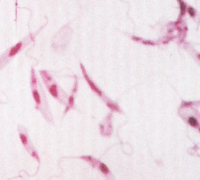

ドノバンリーシュマニア:リーシュマニア・ドノバニ(Leishmania donovani)カラアザールまたは内臓リーシュマニア症の病原体です。アジア(ビルマ、中国東北部、インド、バングラデシュ、スマトラ、タイ)とアフリカ(中央アフリカ、チャ...

肉質鞭毛虫類